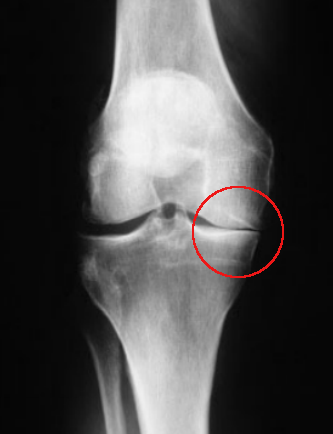

Between the long bones of femur and tibia on X-ray, there is a gap which is the space occupied by the normal meniscus. It shows as a gap because the meniscus is not easily visible on X-ray.

This X-ray actually already shows signs of joint damage, but ignore that for now and just observe the differences in the gap. The red circle shows the gap completely closed - compare the other side which is normal.

Early non-weight-bearing X-rays after a meniscectomy may look completely normal, but taking the X-rays while the joint is being stressed to the side (varus or valgus stress), or while the patient is standing, may demonstrate that the gap is less on the affected side, even though the patient may not be symptomatic.